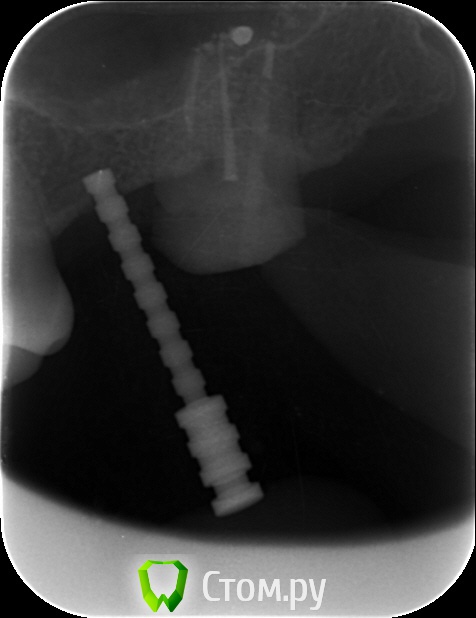

an_ver Опубликовано 29 мая, 2014 Поделиться Опубликовано 29 мая, 2014 Закрытый синус.Набор SCA.SPI 3,75*10 мм 5 Ссылка на комментарий

4ebstom Опубликовано 29 мая, 2014 Поделиться Опубликовано 29 мая, 2014 Имплант недокручен или снимок такой? Ссылка на комментарий

an_ver Опубликовано 29 мая, 2014 Автор Поделиться Опубликовано 29 мая, 2014 Имплант недокручен или снимок такой?Наверно снимок косой)) Счас с формиком ходит.Поставлю коронку отфотаюсь))) Ссылка на комментарий

NickN Опубликовано 29 мая, 2014 Поделиться Опубликовано 29 мая, 2014 Закрытый синус.Набор SCA.SPI 3,75*10 ммНа снимке насадка SCA один в один к МИСовском наборе для компрессии)) Какой графт использовали? Ссылка на комментарий

an_ver Опубликовано 30 мая, 2014 Автор Поделиться Опубликовано 30 мая, 2014 На снимке насадка SCA один в один к МИСовском наборе для компрессии)) Какой графт использовали?Это от набора Мис...немного уплотнил,перед закручиванием Ссылка на комментарий

an_ver Опубликовано 30 мая, 2014 Автор Поделиться Опубликовано 30 мая, 2014 1. Сколько в итоге подняли?2. Имплант какой длины?3. У Вас Rg в кабинете стоит?1. 4 мм 2.3,75*10 мм SPI 3.Rg да,в каждом своя пушка...дорого но удобно..RVG без проводов Дигора Ссылка на комментарий

an_ver Опубликовано 30 мая, 2014 Автор Поделиться Опубликовано 30 мая, 2014 Это от набора Мис...немного уплотнил,перед закручиваниемГрафт МР3 от Остебиола.В наборе есть типа нагнетателя как раньше под амальгаму Ссылка на комментарий